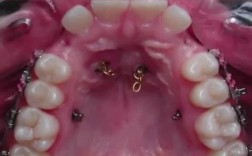

关闭间隙时橡皮链的使用方式(图片描述)

想象一下你看到的正畸关闭间隙的橡皮链图片,通常会是这样的场景:

- 上下颌牙齿排列: 图片会展示患者的上下颌牙齿(模型、口内照片或示意图),通常能看到牙齿上戴着托槽(粘在牙齿表面的小金属片或陶瓷片)。

- 弓丝就位: 一根正畸弓丝(金属丝或镍钛丝)穿过所有牙齿上的托槽槽沟,作为移动牙齿的轨道。

- 橡皮链的连接:

- 图片中会清晰地看到橡皮链被挂在需要移动的牙齿的托槽钩上(托槽上通常有小钩子)。

- 最常见的关闭间隙方式(滑动法):

- 橡皮链的一端挂在需要向前移动的牙齿(通常是后牙,如第一磨牙)的托槽钩上。

- 橡皮链的另一端挂在需要向后移动的牙齿(通常是前牙,如尖牙或切牙)的托槽钩上。

- 橡皮链沿着弓丝的路径连接这两颗(或多颗)牙齿,橡皮链的长度比两颗牙齿托槽钩之间的实际距离要短,这样橡皮链被拉伸后,就会持续产生一个将两颗牙齿相互拉近的力。

- 间隙的位置: 图片中会明确标示出需要关闭的拔牙间隙的位置(通常在拔牙后的区域)。

- 力的方向: 通过橡皮链的拉伸状态,可以直观地看到力的方向是指向间隙中心的,将两边的牙齿拉向间隙。